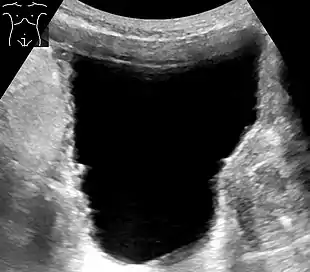

![]() | |

| Urinary retention with greatly enlarged bladder as seen by CT scan. | |

Analysis of urine flow may aid in establishing the type of micturition (urination) abnormality. Common findings, determined by ultrasound of the bladder, include a slow rate of flow, intermittent flow, and a large amount of urine retained in the bladder after urination. A normal test result should be 20-25 mL/s peak flow rate. A post-void residual urine greater than 50 ml is a significant amount of urine and increases the potential for recurring urinary tract infections. In adults older than 60 years, 50-100 ml of residual urine may remain after each voiding because of the decreased contractility of the detrusor muscle.[6] In chronic retention, ultrasound of the bladder may show massive increase in bladder capacity (normal capacity is 400-600 ml).